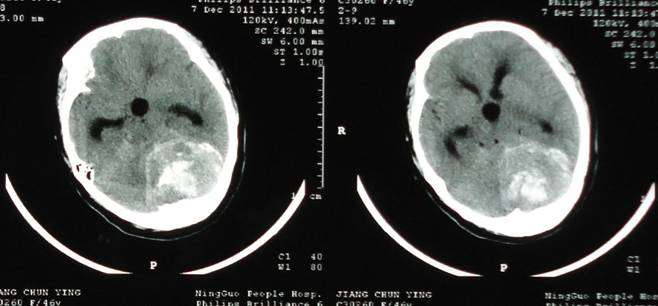

跨入新年,捷報又傳。我院神經(jīng)外科順利成功完成我院首例顱內(nèi)血管介入治療,術(shù)后患者恢復(fù)良好。 患者蔣某,女,49歲,因“左面部陣發(fā)性抽搐伴麻木2月”于2011年12月初入院,入院后診斷為左側(cè)后顱凹巨大腦膜瘤,腫瘤約6*8*7cm大小,且影像學(xué)檢查提示血供豐富,手術(shù)難度巨大。術(shù)前經(jīng)過常規(guī)DSA檢查,顯示腫瘤巨大瘤體由一只主要動脈(左椎動脈腦膜支)供血,如能栓塞此根血管,將會明顯減少腫瘤血供,降低手術(shù)風(fēng)險,從而為患者提供更安全的保障。 經(jīng)與家屬溝通并獲得同意后,12月6日神經(jīng)外科在外院專家的協(xié)助及介入科的緊密配合下予患者行全腦血管造影+瘤體供血血管介入栓塞術(shù),術(shù)中患者目標(biāo)血管開口位置復(fù)雜、血管迂曲細長,難度較大。經(jīng)過數(shù)個小時的奮戰(zhàn),終于成功栓塞目標(biāo)血管,取得滿意的效果。 12月8日,術(shù)后兩天神經(jīng)外科即為該患者行左側(cè)后顱凹巨大腦膜瘤切除術(shù),手術(shù)效果滿意,十余天后痊愈出院。目前,經(jīng)醫(yī)生回訪了解該患者恢復(fù)良好。 該病例為我院首例顱內(nèi)血管介入治療,它的順利完成標(biāo)志著我院神經(jīng)外科在DSA腦血管造影常規(guī)開展基礎(chǔ)上正式進入顱內(nèi)血管介入治療這一全新、復(fù)雜、高風(fēng)險的工作領(lǐng)域,初步完成從介入診斷到介入診斷治療一體化的轉(zhuǎn)變,填補了我市此醫(yī)學(xué)領(lǐng)域的一項空白,必將為我市腦血管病、顱內(nèi)腫瘤患者就近迅捷診斷和治療提供有力保障。 ? ? |